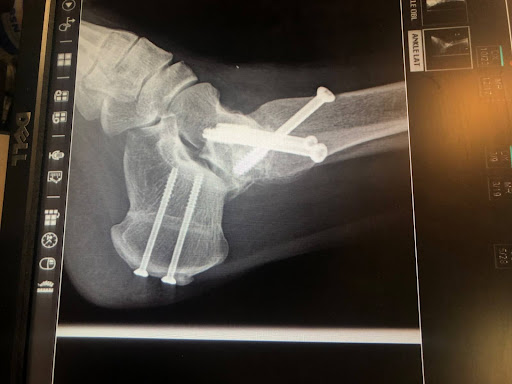

Four years ago, I made the difficult decision to permanently lose mobility in my right ankle to finally free myself from decades of chronic pain. Three failed ankle reconstructions had left me with no other option.

I wanted my life back—simple things, like taking my kids to the zoo, walking my dogs, and moving without constant suffering.

Five months on bedrest, watching my muscles deteriorate. Years of painstakingly rebuilding stamina and retraining my body to walk. The stress and pain got so intense, I developed Shingles (I do not recommend).

Fast forward 4 ½ years from this surgery and I am still in an incredible amount of pain. Like with any kind of inner work, at some point we outgrow our resources and we need to scale again.

Personal transformation is a continuous journey, requiring us to reassess and adapt as we grow. I am back to figuring out what healing looks like for my ankle and even considering a below-the-knee amputation.